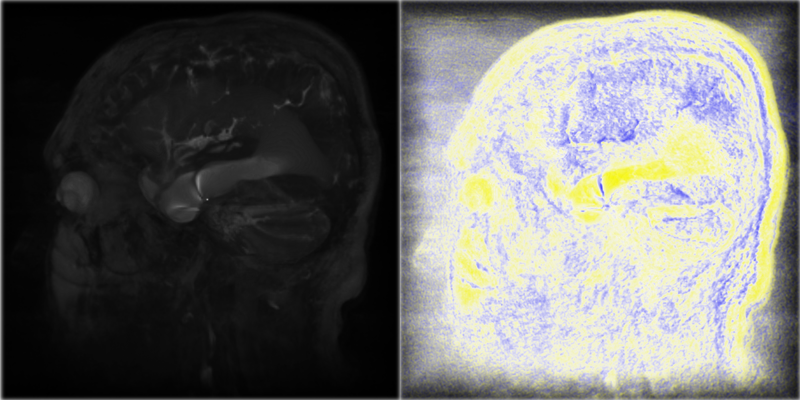

Figure 41.2 shows a basic image of ventricles of the brain on the left and an image of ventricles of the brain using BoundaryEnhancementVolumeStyle on the right.

Figure 41.2 — On the left, the ventricle with default render style and default field values. On the right, the ventricle using BoundaryEnhancementVolumeStyle with default values: boundaryOpacity=0.9, opacityFactor=2, and retainedOpacity=0.2.